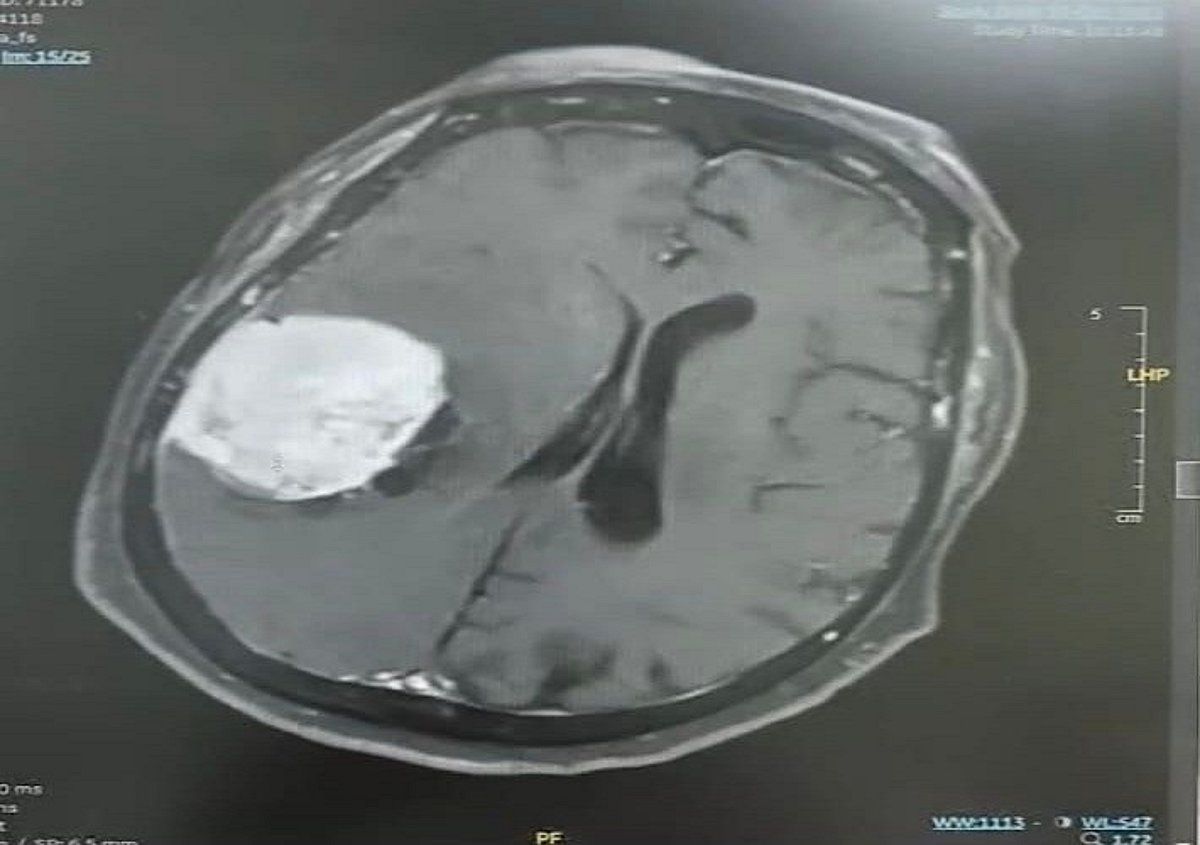

تمكّن فريق طبي متخصص بمستشفى ينبع العام عضو تجمع المدينة المنورة الصحي من إجراء عملية نوعية دقيقة لاستئصال ورم دماغي كبير بحجم (٥×٥×٤ سم) لسيدة تبلغ من العمر 80 عامًا، كانت تعاني من صداع مزمن وضعف متزايد في الجانب الأيسر من الجسم حتى أصبحت غير قادرة على الحركة وطريحة الفراش.

وأوضح تجمع المدينة المنورة الصحي أن المستفيدة راجعت المستشفى وهي تعاني من الأعراض المذكورة، وبعد إجراء الفحوصات السريرية وصور الرنين المغناطيسي تبيّن وجود ورم كبير في الجهة الجدارية اليمنى من الدماغ، وبعد التنسيق مع الأقسام ذات العلاقة واستكمال التحضيرات الطبية، أُدخلت المريضة إلى غرفة العمليات حيث نجح الفريق الطبي – بفضل الله – في استئصال الورم بالكامل بدقة عالية دون مضاعفات.